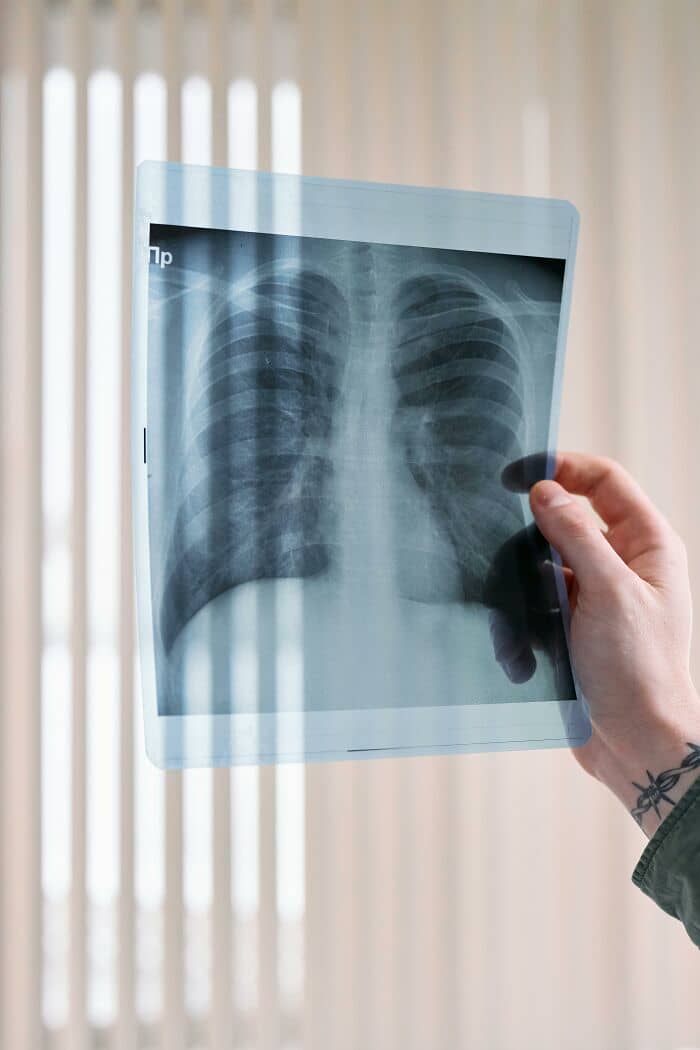

Whenever you have medical test or scan, ask for a copy of the report.

Get copies of your hospital discharge summaries.

Keep all of it in a binder, newest stuff at the front. Take it with you to appointments just in case.

This is especially important for women but it can be helpful for everyone.